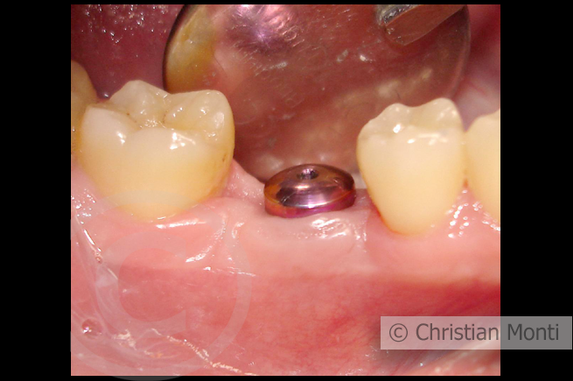

EDENTULIA SINGOLA

Impianto dilazionato in sostituzione di un molare inferiore